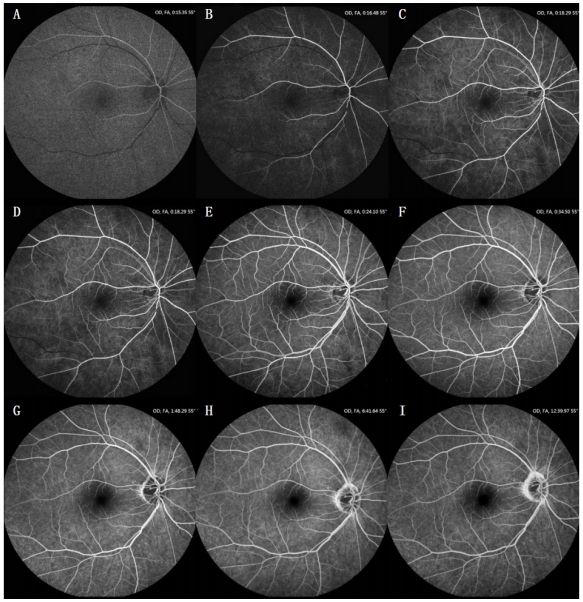

2) 根据病情和造影目的选择主照眼和造影重点。以主要病灶位于后极部的成人患眼为例:造影开始前镜头聚焦于主照眼后极部,建议计时至6~8 s开始(儿童和婴幼儿应在注射造影剂当时开始)以至少1~2 s的频率连续拍摄至主照眼视网膜静脉完全回流(如果双眼后极部均有病灶,且病情对视网膜血流动力学观察要求不高时可双眼穿插拍摄)。其后根据需要断续拍摄主照眼后极部和对侧眼后极部,再拍摄双眼周边各方位;过程中应穿插拍摄主照眼后极部,重点关注主要病变部位荧光变化。一般分早(1 min内)、中(1~10 min)、晚(10~15 min)三个时期拍摄造影图像至计时15 min左右(图1)。拍摄过程中应随时调整曝光或增益以获取较好对比度的图片。如果拍摄者用手固定患者眼睑,拍摄过程中应适当给予患者眨眼间歇,以免泪液积聚造成造影图像模糊。

(A)动脉期;(B-E)动静脉期;(F)静脉早期;(G, H)静脉中期;(I)静脉晚期。

(A) Arterial phase; (B-E) arteriovenous phase; (F) early venous phase; (G, H) mid-venous phase; (I) late venous phase.

1) 预试验观察无阳性反应,首选肘前静脉,建议用静脉留置针建立静脉通道,确认静脉通道通畅,更换为造影剂原液注射器,嘱患者放松,特别是肩肘部位;快速注入造影剂(注射时长约5 s,对于血管条件差、病情上对眼底血流动力学观察要求不高的患者可放宽至8~10 s),注射开始的同时启动计时。2) 根据病情和造影目的选择主照眼和造影重点。以主要病灶位于后极部的成人患眼为例:造影开始前镜头聚焦于主照眼后极部,建议计时至6~8 s开始(儿童和婴幼儿应在注射造影剂当时开始)以至少1~2 s的频率连续拍摄至主照眼视网膜静脉完全回流(如果双眼后极部均有病灶,且病情对视网膜血流动力学观察要求不高时可双眼穿插拍摄)。其后根据需要断续拍摄主照眼后极部和对侧眼后极部,再拍摄双眼周边各方位;过程中应穿插拍摄主照眼后极部,重点关注主要病变部位荧光变化。一般分早(1 min内)、中(1~10 min)、晚(10~15 min)三个时期拍摄造影图像至计时15 min左右(图1)。拍摄过程中应随时调整曝光或增益以获取较好对比度的图片。如果拍摄者用手固定患者眼睑,拍摄过程中应适当给予患者眨眼间歇,以免泪液积聚造成造影图像模糊。

图1 一例右眼后极部FFA

Figure 1 FFA of the posterior pole of a right eye